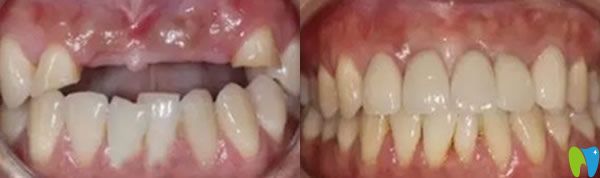

三個月后,我們又來到成都瑞爾口腔,醫(yī)生說恢復(fù)的很不錯,牙槽骨和種植體已經(jīng)緊密結(jié)合,可以安裝基臺,戴上牙冠后,牙齒咀嚼功能恢復(fù)了,可承受正常的咀嚼力量,美觀上幾乎和自然牙一樣。郝亦工醫(yī)生建議后期一定要保持好口腔衛(wèi)生健康,細(xì)心呵護(hù),這樣能夠保證種植牙的使用壽命。

在成都瑞爾口腔種植牙技術(shù)解決了老公牙齦萎縮,精神面貌也好了,不再像個糟老頭,整個人也精神起來啦!